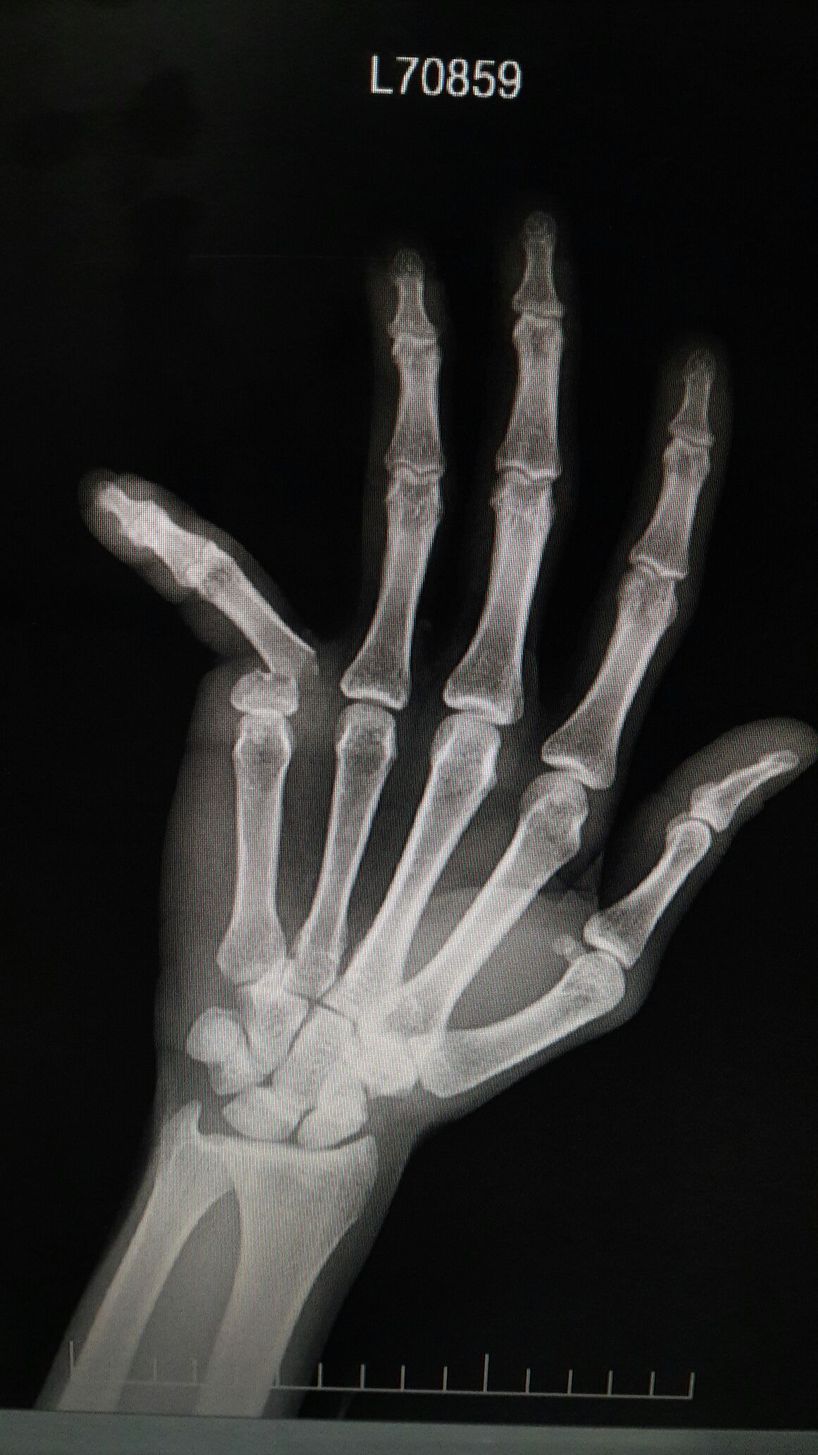

Finger Fracture😵

Emergency

Trauma

Fracture

Orthopedics